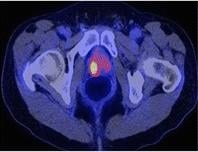

June 24, 2015 - Siemens' PETNET Solutions, a wholly owned subsidiary of Siemens Healthcare, announced it will provide clinical researchers in the greater New York City area with access to gallium-68-labeled prostate-specific membrane antigen (Ga-68 labeled PSMA). This investigational tracer is being studied for prostate cancer imaging using positron emission tomography/computed tomography (PET/CT) in clinical trials throughout the world.

Prostate cancer is the second most frequently diagnosed cancer among men in the United States. An estimated 220,000 men are expected to be diagnosed with the disease this year, with approximately 15,000 in New York state alone. Recent hypotheses regarding the variation and diversity of prostate cancer suggest that all variants should not be treated equally – underscoring a need for expanded classification of the disease through imaging and biopsy methods.